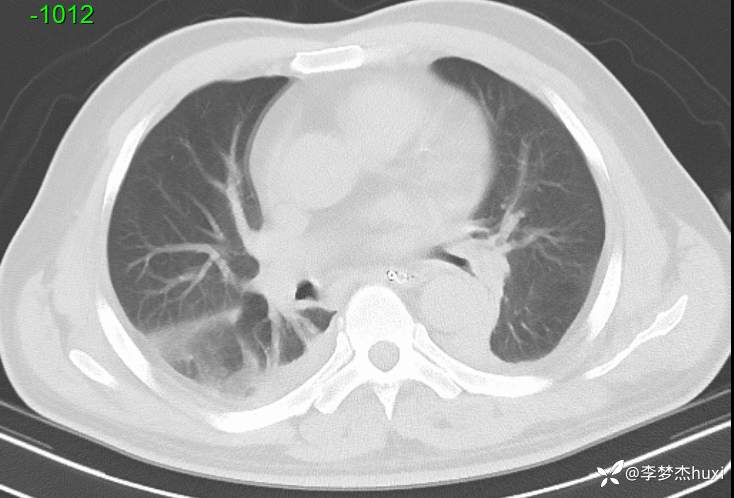

【现病史及既往史】: 1.现病史:患者老年 男,于入院前1天,患者在骑自行车时发生车祸,致伤头部,右颞顶部受力,伤后患者意识不清,右侧外耳道及右侧鼻腔出血,院外未处理,急来我院急诊就诊,查头颅CT示:右侧额颞顶枕部硬膜下血肿,颅内积气,蛛网膜下腔出血,左侧额颞部硬膜下出血?脑干密度减低,右侧颞顶部头皮软组织肿胀,右侧颞、顶骨骨折,右侧乳突小房密度增高。右侧外耳道密度增高。右侧蝶窦密度增高。胸部CT+三维重建示:双肺索条,双肺透过度欠均匀,双肺纹理增重,主动脉钙化,冠状动脉钙化。急诊以“闭合性颅脑损伤重型”收入我科。

【治疗经过及结果】:辅助检查:查头颅CT示:右侧额颞顶枕部硬膜下血肿,颅内积气,蛛网膜下腔出血,左侧额颞部硬膜下出血?脑干密度减低,右侧颞顶部头皮软组织肿胀,右侧颞、顶骨骨折,右侧乳突小房密度增高。右侧外耳道密度增高。右侧蝶窦密度增高。胸部CT+三维重建示:双肺索条,双肺透过度欠均匀,双肺纹理增重,主动脉钙化,冠状动脉钙化。